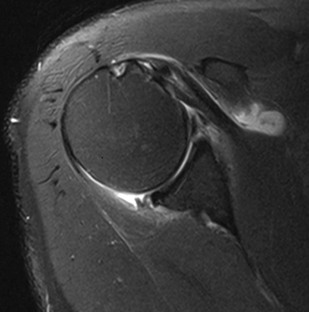

Although conventional MRI is established as the imaging modality of choice in the evaluation of shoulder impingement syndrome, MRA is accepted as the method of choice for the evaluation of glenohumeral instability.22,23 Many of the lesions associated with instability are subtle and may undergo partial healing. This situation, coupled with the fact that the normal anatomic structures of the shoulder lie in close proximity, can make the diagnosis of these lesions difficult even with high-quality conventional MRI.58-62 MRA, on the other hand, is performed by distending the joint with fluid (saline solution or dilute gadolinium), which more accurately depicts subtle labral tears, cartilage and ligamentous abnormalities, and partial-thickness tears of the undersurface of the rotator cuff. The standard injection technique for MRA of the shoulder is described in previous sections. About 12 to 14 mL of gadolinium diluted 1 : 200 with normal saline solution or 1% lidocaine is injected. Imaging protocols vary, but a standard set of imaging sequences typically includes T1-weighted images with frequency-selective fat saturation in the axial, oblique sagittal, and oblique coronal planes. The T1-weighted images have a high signal/noise ratio, resulting in the anatomic detail that is critical in detecting the subtle lesions associated with glenohumeral instability. A T2-weighted sequence performed in the oblique coronal plane is the most important sequence for depicting rotator cuff abnormalities. A T2-weighted sequence may also be helpful in detecting other pathologic processes, such as a paralabral cyst or bone marrow edema (Fig. 44-7, A and B). The ABER view may be added to the standard imaging protocol for any patient thought to have an anterior labral pathologic process.54

Anterior and lateral downward sloping of the anterior acromion can also narrow the supraspinatus outlet and potentially result in impingement.80,81 Anterior downward sloping (see Fig. 44-11, B) is demonstrated on oblique sagittal MRI; lateral downward sloping (see Fig. 44-11, C) is best seen on the oblique coronal images. An enthesophyte (Fig. 44-12) extending off the anteroinferior aspect of the acromion can also be clearly demonstrated on MRI. It typically appears as a marrow-containing osseous excrescence, which should have MRI signal characteristics similar to those of the adjacent acromion marrow (bright on T1-weighted images). Potential pitfalls include the attachment of the coracoacromial ligament and the deltoid tendon insertion (see Fig. 44-11, A and C) on the anterior acromion. These structures may mimic an osseous excrescence, but they can be differentiated from enthesophytes because they lack marrow signal and appear dark on all pulse sequences. The acromion should also be evaluated for os acromiale (Fig. 44-13), which is an accessory ossification center along the outer edge of the anterior acromion. It is normally fused by 25 years of age. An association exists between persistent os acromiale and impingement of the rotator cuff.82-86 The deltoid muscle attaches to the inferior aspect of the accessory ossicle, and contraction of the deltoid results in a downward motion of the unstable segment, potentially leading to impingement of the underlying rotator cuff. Os acromiale is demonstrated best on axial images (see Fig. 44-7, A), but it can also be seen on oblique sagittal or oblique coronal images (see Fig. 44-7, B),85 on which it should not be confused with the adjacent AC joint. MRI signs of instability of the os acromiale include fluid signal within the synchondrosis or sclerosis, cystic change, or marrow edema on either side of the synchondrosis (Box 44-2).